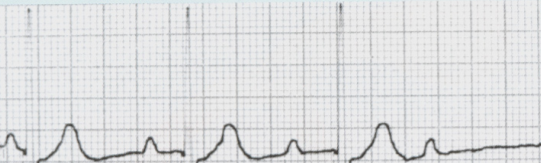

What is depicted by the EKG

Atrial Flutter

Atrial Flutter w/ 2:1 AV Block